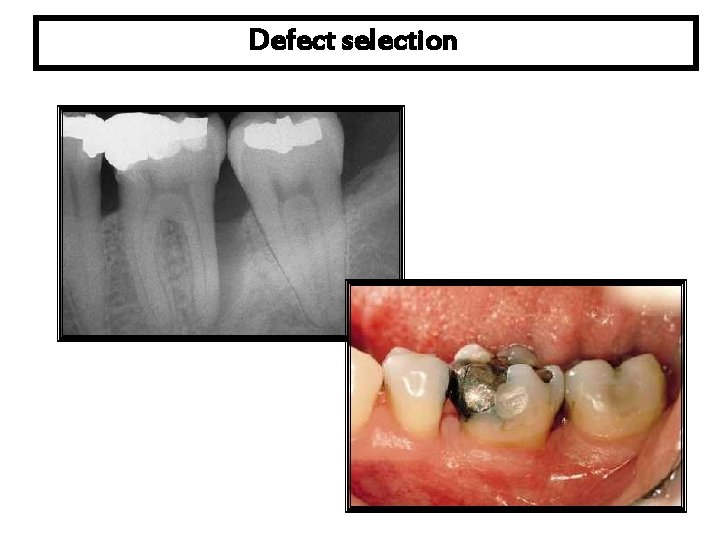

Defect selection

Flap design A sulcular incision full thickness flap is reflected. A three wall intrabony defect is visualized at the distal of the first molar.